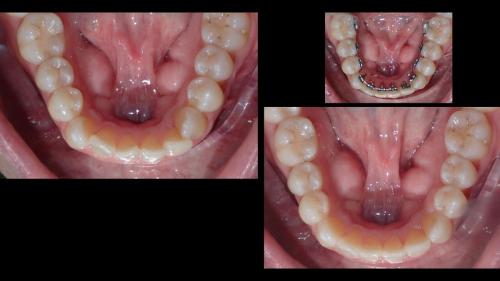

large-Ortodoncia Lingual

large-Ortodoncia lingual invisible

large-Lingual